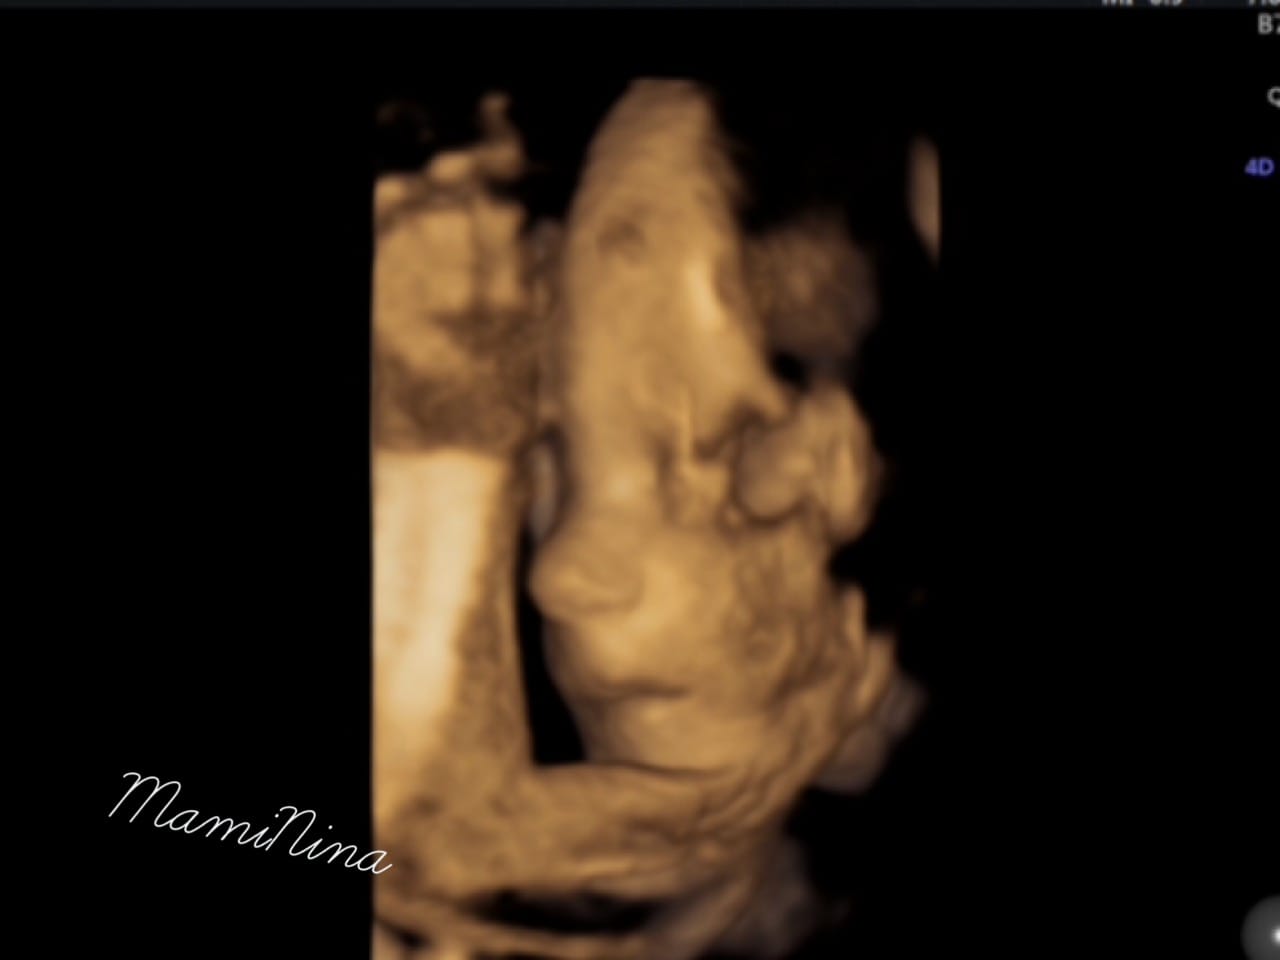

Seveda pa prilagam tudi 4D ultrazvok male zaspanke, ki je načeloma ves čas zelo aktivna, tokrat pa je na pregledu bolj ali manj počivala.

In resnično nam ni prav nič žal. Videli smo vse in to zelo dobro. Obrazek je seveda gospodična precej pokrivala, tako kot ga je tudi njena sestrica. In ne le to, prav tako kot sestrica, je tudi tale gospodična obrnjena v desno, pred obrazkom se nahaja tudi ena nogica in seveda kraljuje na svoji mali ritki.

Srček utripa z 132 udarci, mala pa ima že približno nekje 830 g (če bo teža naraščala tako kot do sedaj, predvidevam, da bo precej lahka, seveda pa so tudi njene mere manjše).